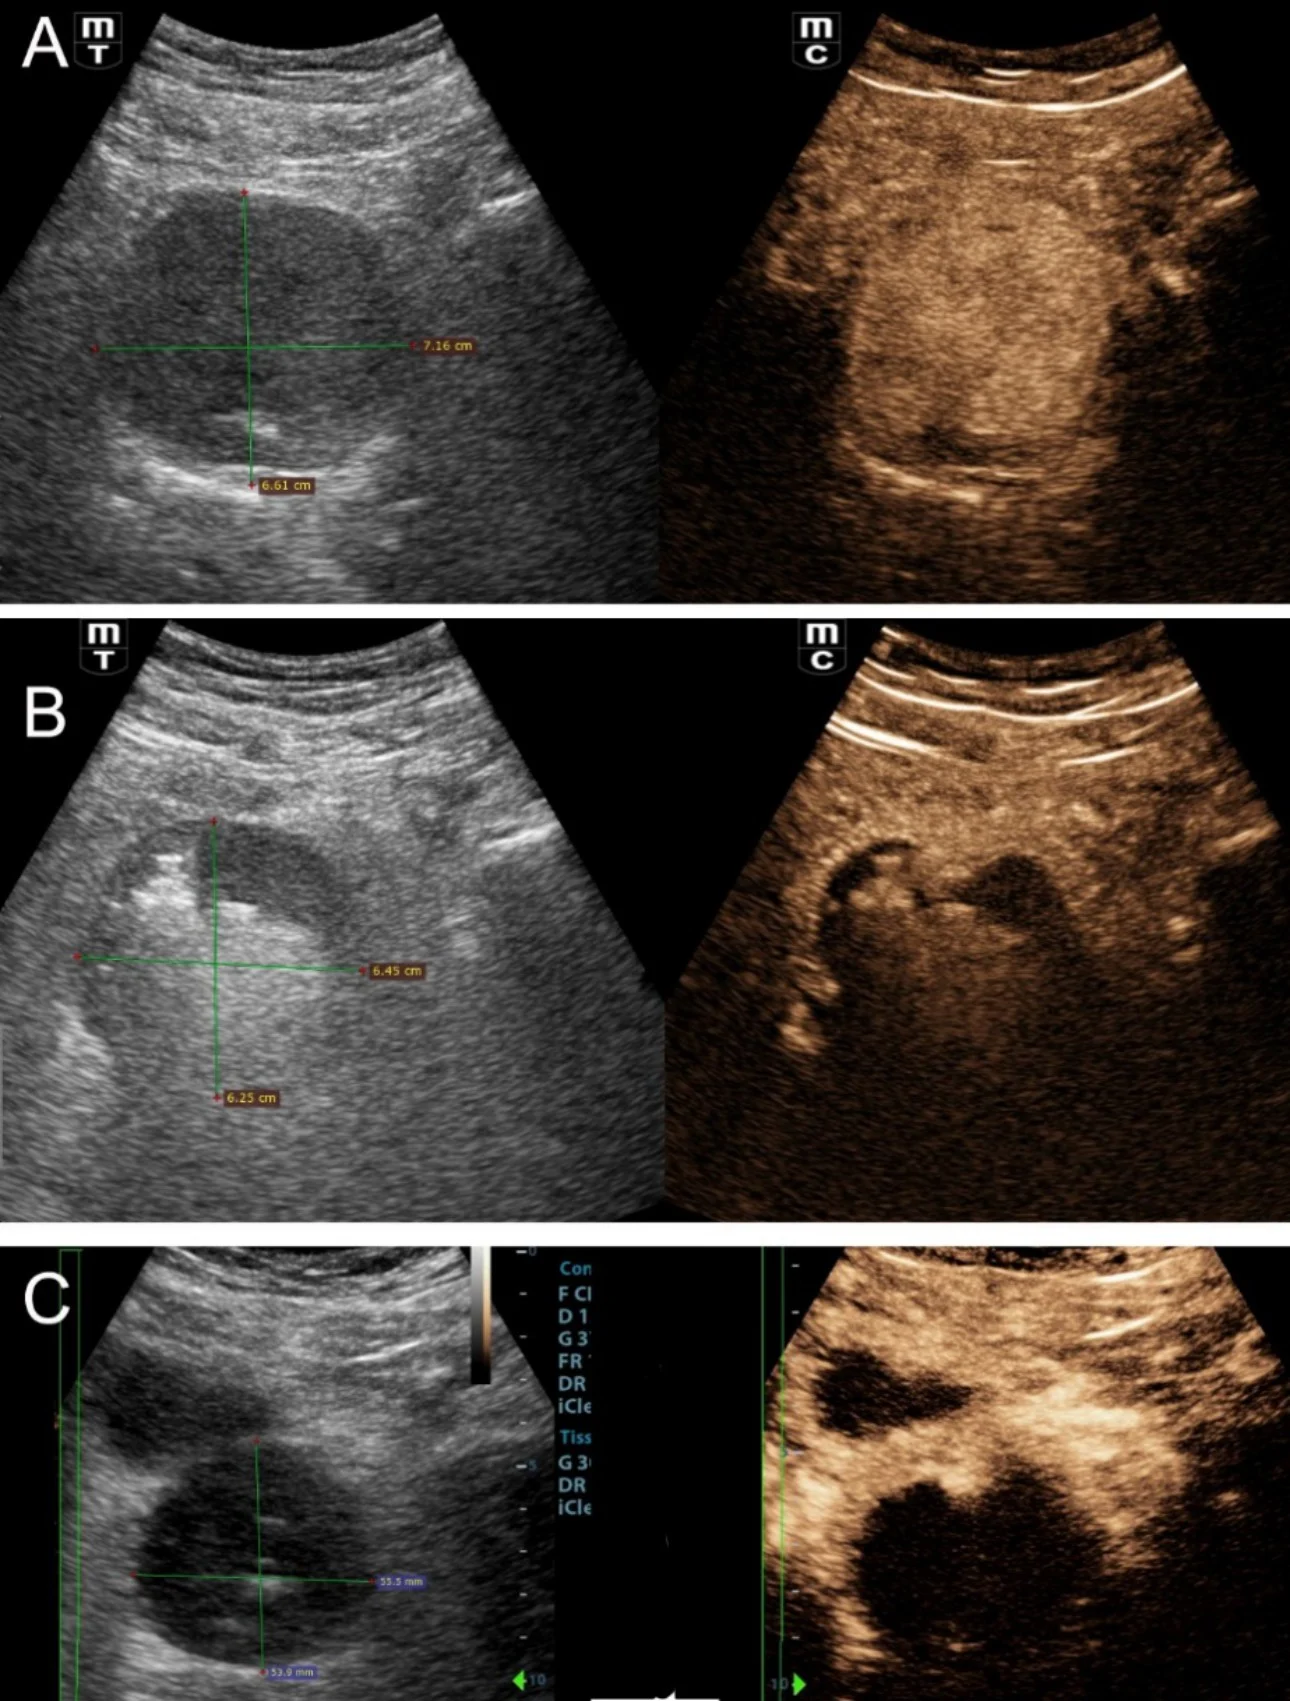

In addition to the aforementioned morphologic evaluation, contrast-enhanced US (CEUS) with intravenous administration of a second-generation echo-enhancer (SonoVue, Bracco, Milan, Italy) can be applied to study the hemodynamic and perfusional changes that occur in the prostate post PAE [3,4]. Prostatic infarcts can be easily detected as enhancement defects immediately post PAE (Fig 1); they are considered as a reliable sign of the local efficacy of PAE and they also correlate with clinical success.

Figure1: Representative transabdominal US and CEUS images of the prostate pre and post PAE. Images are shown in a ‘split-screen’ mode with unenhanced, reference B-mode image on the left, and the corresponding CEUS image on the right. A: At baseline, almost homogeneous enhancement of the entire gland is noted. B: One day post PAE, extensive irregular echogenicities are detected by US in both prostatic lobes. The echogenicities are also partially present in the CEUS image, which additionally shows lack of enhancement (infarction) in the largest part of the prostate. C: One month post PAE, US shows almost complete disappearance of the echogenicities and reduction in prostate size. CEUS shows persistent lack of enhancement in the largest part of the prostate.